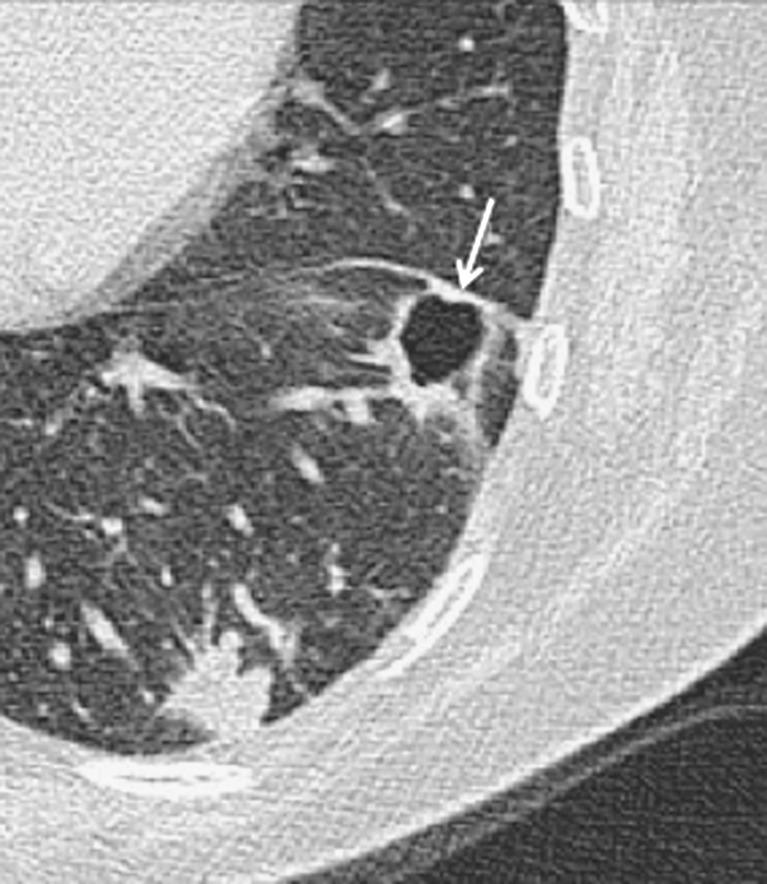

A lung cyst is defined as a round parenchymal lucency or area of low attenuation with a thin wall. They are not uncommon findings on high-resolution (HR) thoracic computed tomography (CT) and when identified, they require explanation. The differential diagnosis for diseases characterised by lung cysts is broad ranging from isolated chest disorders to rare multisystem diseases. This article provides a practical approach for evaluating lung cysts on HRCT, highlighting disorders in which the HRCT findings can be diagnostic as well as conditions where correlation with clinical history or biopsy is required.

肺囊肿被定义为圆形的实质透亮区或具有薄壁的低衰减区域。它们在高分辨率(HR)胸部计算机断层扫描(CT)上并非罕见的发现,一旦被识别,就需要进行解释。以肺囊肿为特征的疾病的鉴别诊断范围广泛,从孤立的胸部疾病到罕见的多系统疾病。本文提供了一种在HRCT上评估肺囊肿的实用方法,重点介绍了HRCT表现具有诊断价值的疾病以及需要结合临床病史或活检的情况。